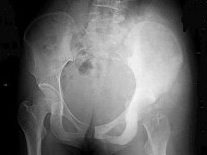

16岁女性患者,左臀部疼痛伴发热2个月,X线检查如图所示,最佳的诊断是()

A:左髂骨成骨肉瘤

B:左髂骨急性化脓性骨髓炎

C:左髂骨软骨肉瘤

D:左髂骨网状细胞肉瘤

E:左髂骨软骨瘤